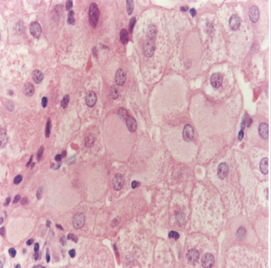

毛玻璃样肝细胞 多见于HBsAg携带者及慢性肝炎患者的肝组织。镜下见肝细胞体积稍大,胞浆内充满嗜酸性细颗粒状物质,不透明似毛玻璃样故称毛玻璃样肝细胞。用免疫组化染色呈HBsAg阳性反应,证实肝细胞浆内有HBsAg存在。电镜显示光面内质网内有大量HBsAg,呈线状或小管状。

(1)肝细胞再生:肝细胞坏死时,邻近的肝细胞可通过直接或间接分裂而再生修复。在肝炎恢复期或慢性阶段则更为明显。再生的肝细胞体积较大,核大而染色较深,有的可有双核。慢性病例在门管区尚可见细小胆管的增生。